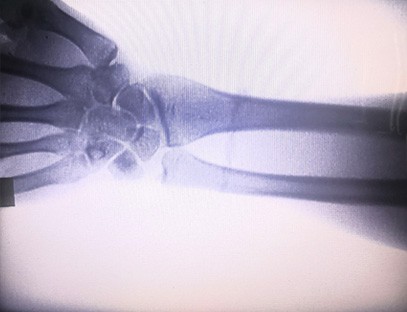

Il-Magni Ortopediċi tar-Raġġi X tagħna huwa prodott ta 'kwalità għolja li kien iddisinjat partikolarment għall-immaġini ortopediċi. Jista 'jintuża għad-dijanjosi u l-ippjanar tat-trattament ta' kundizzjonijiet ortopediċi varji, inklużi ksur, dislokazzjonijiet, artrite u tumuri fl-għadam. Hija mgħammra b'teknoloġija avvanzata tar-raġġi-X li tippermetti immaġini ta 'kwalità għolja b'espożizzjoni mnaqqsa għar-radjazzjoni. Il-magna għandha sistema ta 'immaġni b'riżoluzzjoni għolja u tista' taqbad immaġini ta 'kwalunkwe struttura tal-għadam b'ċarezza kbira.

Il-Magna Ortopedika tar-Raġġi X tagħna tista 'tintuża f'diversi speċjalitajiet mediċi, inklużi l-ortopedija, newroloġija, u mediċina ta' emerġenza. Ħafna drabi jintuża għall-osservazzjoni fluworoskopika ta 'għadam tar-riġlejn umani, Sptarijiet veterinarji u domestiċi, Trattament ta' feruti f'siti sportivi, bini, vapuri tal-oċean, żoni remoti u siti tal-kamp militari. Uħud mill-applikazzjonijiet kliniċi jinkludu:

1. Dijanjosi ta 'ksur, dislokazzjonijiet, u korrimenti oħra fl-għadam.

2. Evalwazzjoni ta 'mard tal-ġogi bħal artrite, mard tal-ġogi deġenerattiv, u osteoporożi.